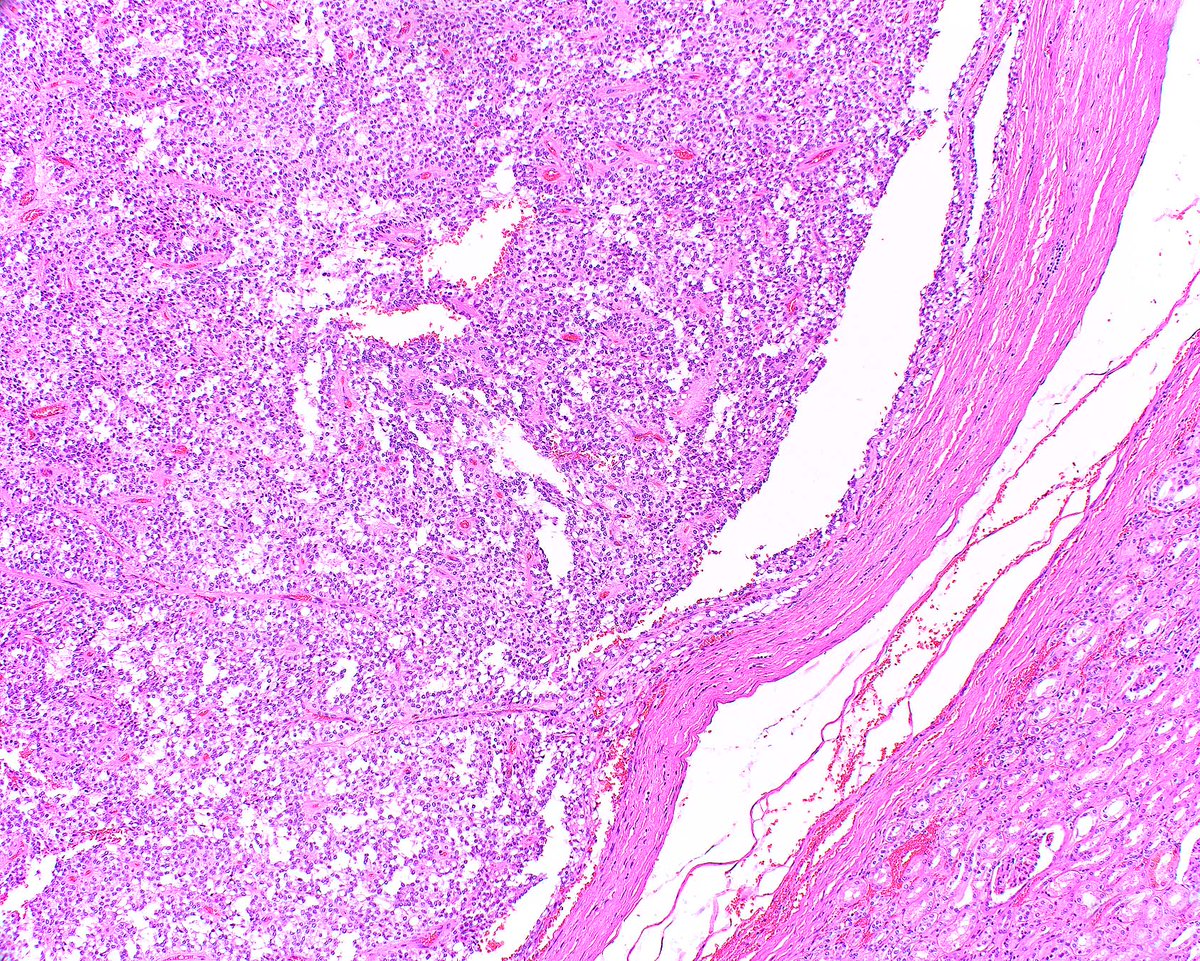

This is an ordinary mantle cell lymphoma of the colon - presenting as multiple nodular areas. However, more aggressive subtypes are in a spectrum with large B cell lymphomas.

Li S, Tang G, Jain P, Lin P, Xu J, Miranda RN, Cheng J, Yin CC, You MJ, Wang ML, Medeiros LJ. SOX11+ Large B-Cell Neoplasms: Cyclin D1-Negative Blastoid/Pleomorphic Mantle Cell Lymphoma or Large B-Cell Lymphoma? Mod Pathol. 2024 Feb;37(2):100405.PMID: 38104893.